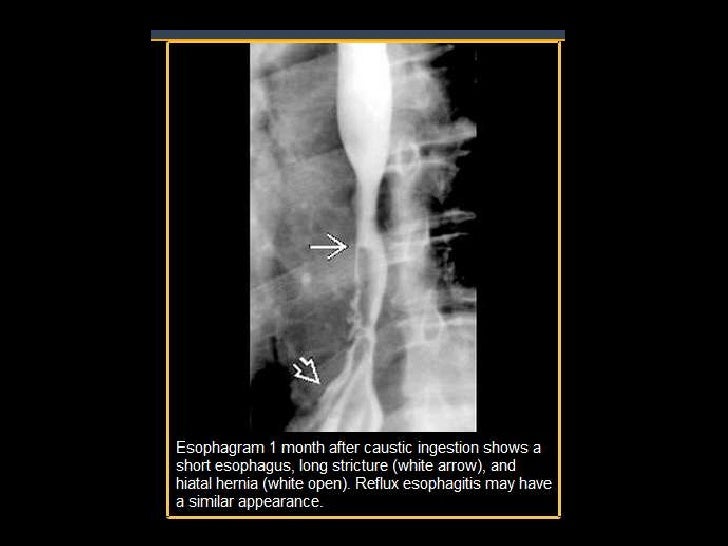

Figure 2Benign Strictures of the Esophagus and Gastric Outlet Caustic Esophagitis — esophageal motility studies report low amplitude and nonperistaltic. — caustic substances injure tissue by means of a chemical reaction on direct physical contact. — caustic ingestion can cause severe injury to the esophagus and the stomach. — caustic ingestions are seen most often in young children between one and three years of age and can. Caustic Esophagitis.